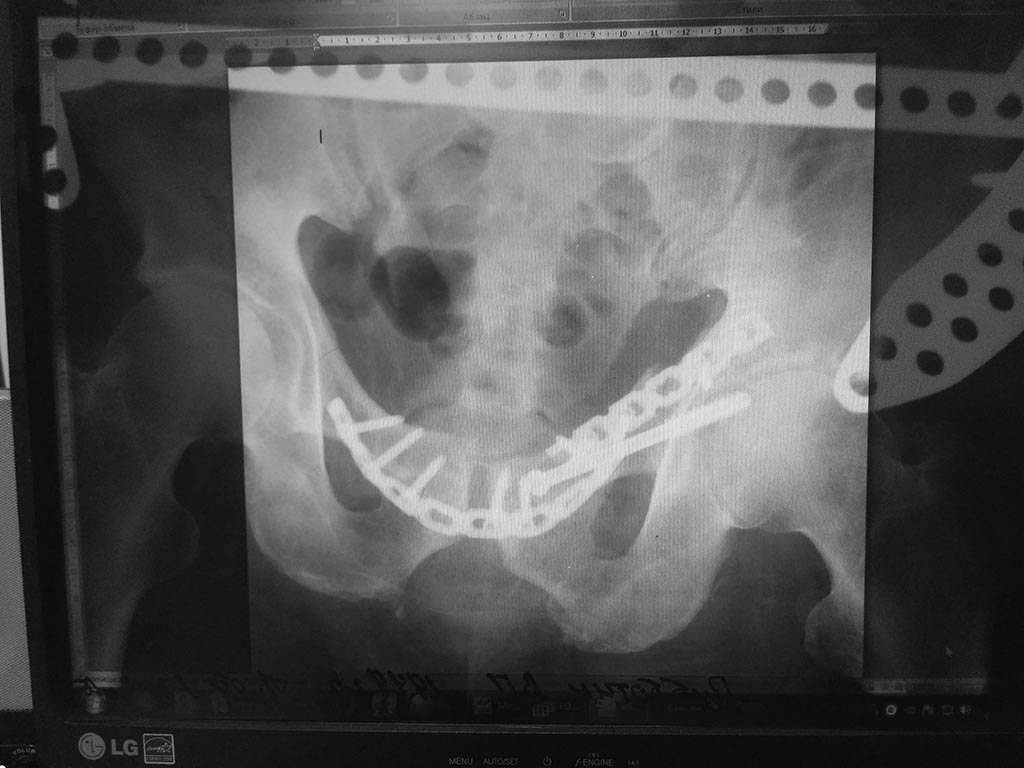

Re: Таз

послал Бек 23 Октябрь 2017, 00:10

Больной выписан с улучшением швы удалены. Но через неделю после выписки вновь поступил с расхождением после операционной раны надлобковой области 0,4х0,3см с гнойным выделением . Выполнено вскрытие гнойника получено около 200мл гнойное отделяемое. Туалет раны , через неделю выполнено удаление МОС . АВФ оставлен